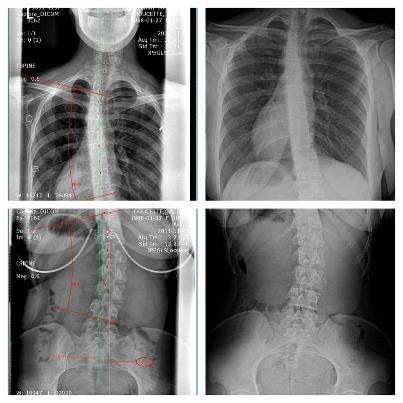

In questo articolo, scritto da Lu Mueller-Kaul, viene fatto uno studio sugli effetti del Rolfing su pazienti che presentano questa deformazione della colonna; l'articolo mostra immagini "prima e dopo" il ciclo di Rolfing® e evidenzia come il Rolfing possa avere effetti benefici sui pazienti trattati.